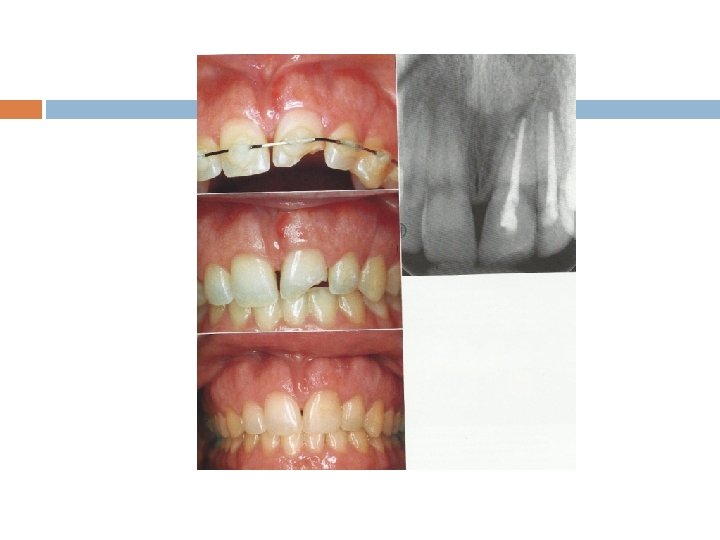

Radiographic examination Presence of root fracture Degree of extrusion or intrusion Presence of preexisting periapical disease Extent of root development Size of the pulp chamber and root canal Presence of jaw fractures Tooth fragments and foreign bodies lodged in soft tissue

有幾處有 Fracture lines